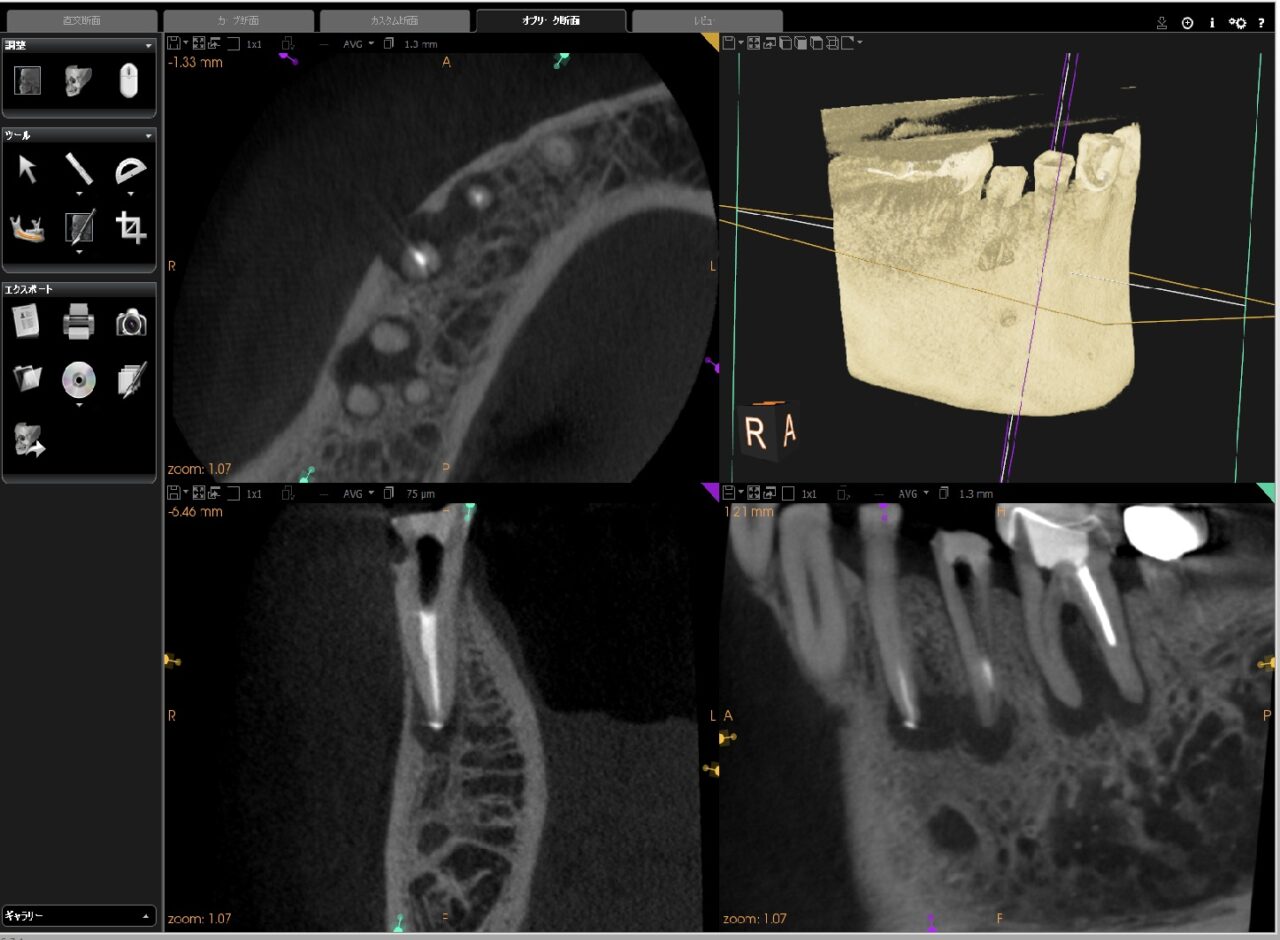

■術後のCT画像

#44は、根尖までバイオセラミック製剤が入っている事が確認できる。

#45も同様にこのCTのカットでは確認できないが、根尖までバイオセラミックが根管充填されています。

そのため、数ヶ月後には骨再生が確認される見込みです。